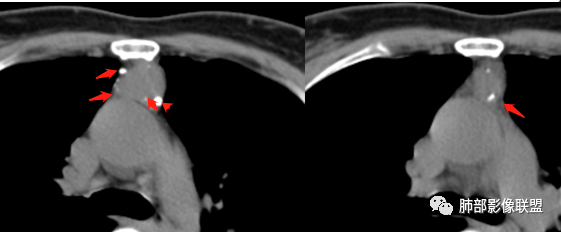

南边:定位前纵隔没问题

边缘多发条状、线样、结节状钙化

南边:边界尚清,位于残留胸腺组织内

中央结节状强化, 类似于血管强化

定性:偏良性病变,血管瘤?胸腺瘤?

前纵隔海绵状血管瘤的影像学特征包括:①发生于前纵隔的圆形、类圆形、不规则肿块影,边界清晰,与邻近结构分界清晰;②CT上呈稍低密度影,内见小结节状、小片状、针尖状的钙化灶,钙化灶、静脉石影是海绵状血管瘤的特征性表现。③增强后大多数肿块可显示肿块的范围及供血情况,动脉期病灶边缘呈点片状强化,静脉期及延迟期逐步向内填充,呈渐进性强化等典型特征,部分不强化或轻度强化,部分增强 后片状强化,强化程度与邻近血管相仿;血管瘤强化方式与肿块内组织成分、血窦内血栓、血流等因素有关;Moran等研究表明,肿块强化不均匀或呈轻度强化的原因可能与扩张的血窦腔内组织平滑肌增殖及炎性纤维化有关;肿块血管样强化可提示海绵状血管瘤。前纵隔海绵状血管瘤需与畸胎瘤、胸腺瘤、胸内甲腺肿、神经内分泌肿瘤等进行鉴 别 断:①畸胎瘤多呈混杂密度影,内有脂肪、毛发、钙化灶及水样密度;②胸腺瘤呈结节状、团块状影,密度较均匀,增强后强化较均匀,与周围组织分界清晰;③胸内甲状腺肿位于前上纵隔,平扫密度常较高,可见其上端与颈部甲状腺相连;④神经内分泌肿瘤多伴坏死囊变,点片状钙化,形态常呈分叶状或 不规则形,增强后肿瘤实性部分强化显著。

综上所述,海绵状血管瘤发生在纵隔非常罕见,且缺乏典型的临床症状及特异性影像, 应从肿块的位 置、大小、形态、与周围组织的 关 系 以及CT平扫、增强特点进行分析,如前纵隔肿块内有钙化灶、静脉石、增强后点片状血管样强化及渐进性强化等特点,应考虑纵隔海绵状血管瘤的可能;薄层CT及其多平面重组有利于发现细小钙化灶,而动态增强CT扫描能更好显示肿块内血管强化,有助于术前诊断与鉴别诊断。